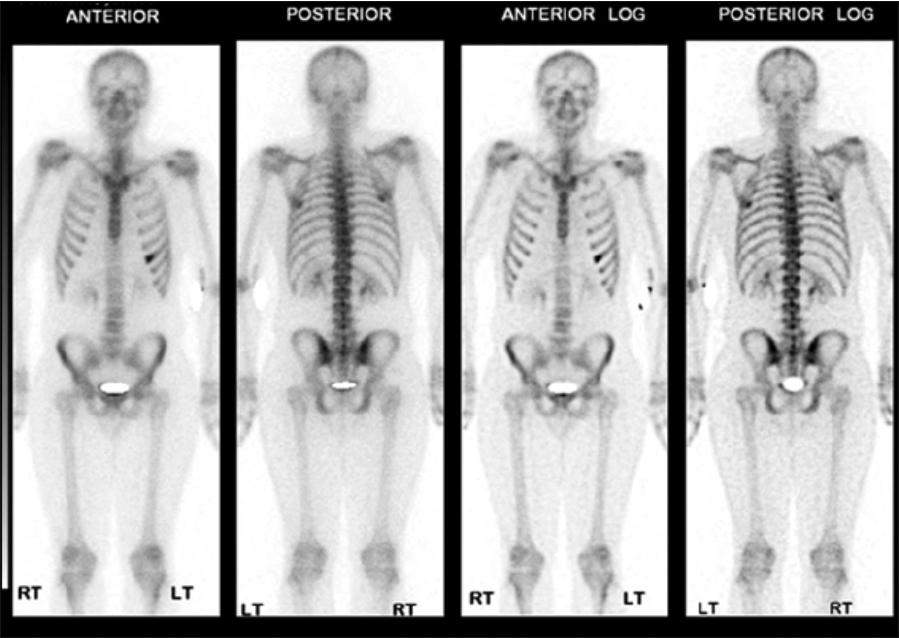

Figure 4: Nuclear imaging of whole body scan – radioisotope uptake of the sixth rip on anterior view

Figure 4: Nuclear imaging of whole body scan – radioisotope uptake of the sixth rip on anterior view(click to enlarge)

Work up for endocarditis and abscess elsewhere was unremarkable. An ultrasound-guided needle aspiration of the swelling was inconclusive. An MRI thorax was arranged and showed periosteal enhancement of the sixth anterior rib, suggestive of infectious process (osteomyelitis) with an intramuscular abscess (Figure 3). The findings were reconfirmed by a whole body isotope scan with no other hot spot (Figure 4). The patient was treated for osteomyelitis for six weeks as per hospital guidelines. The patient responded clinically and biochemically.